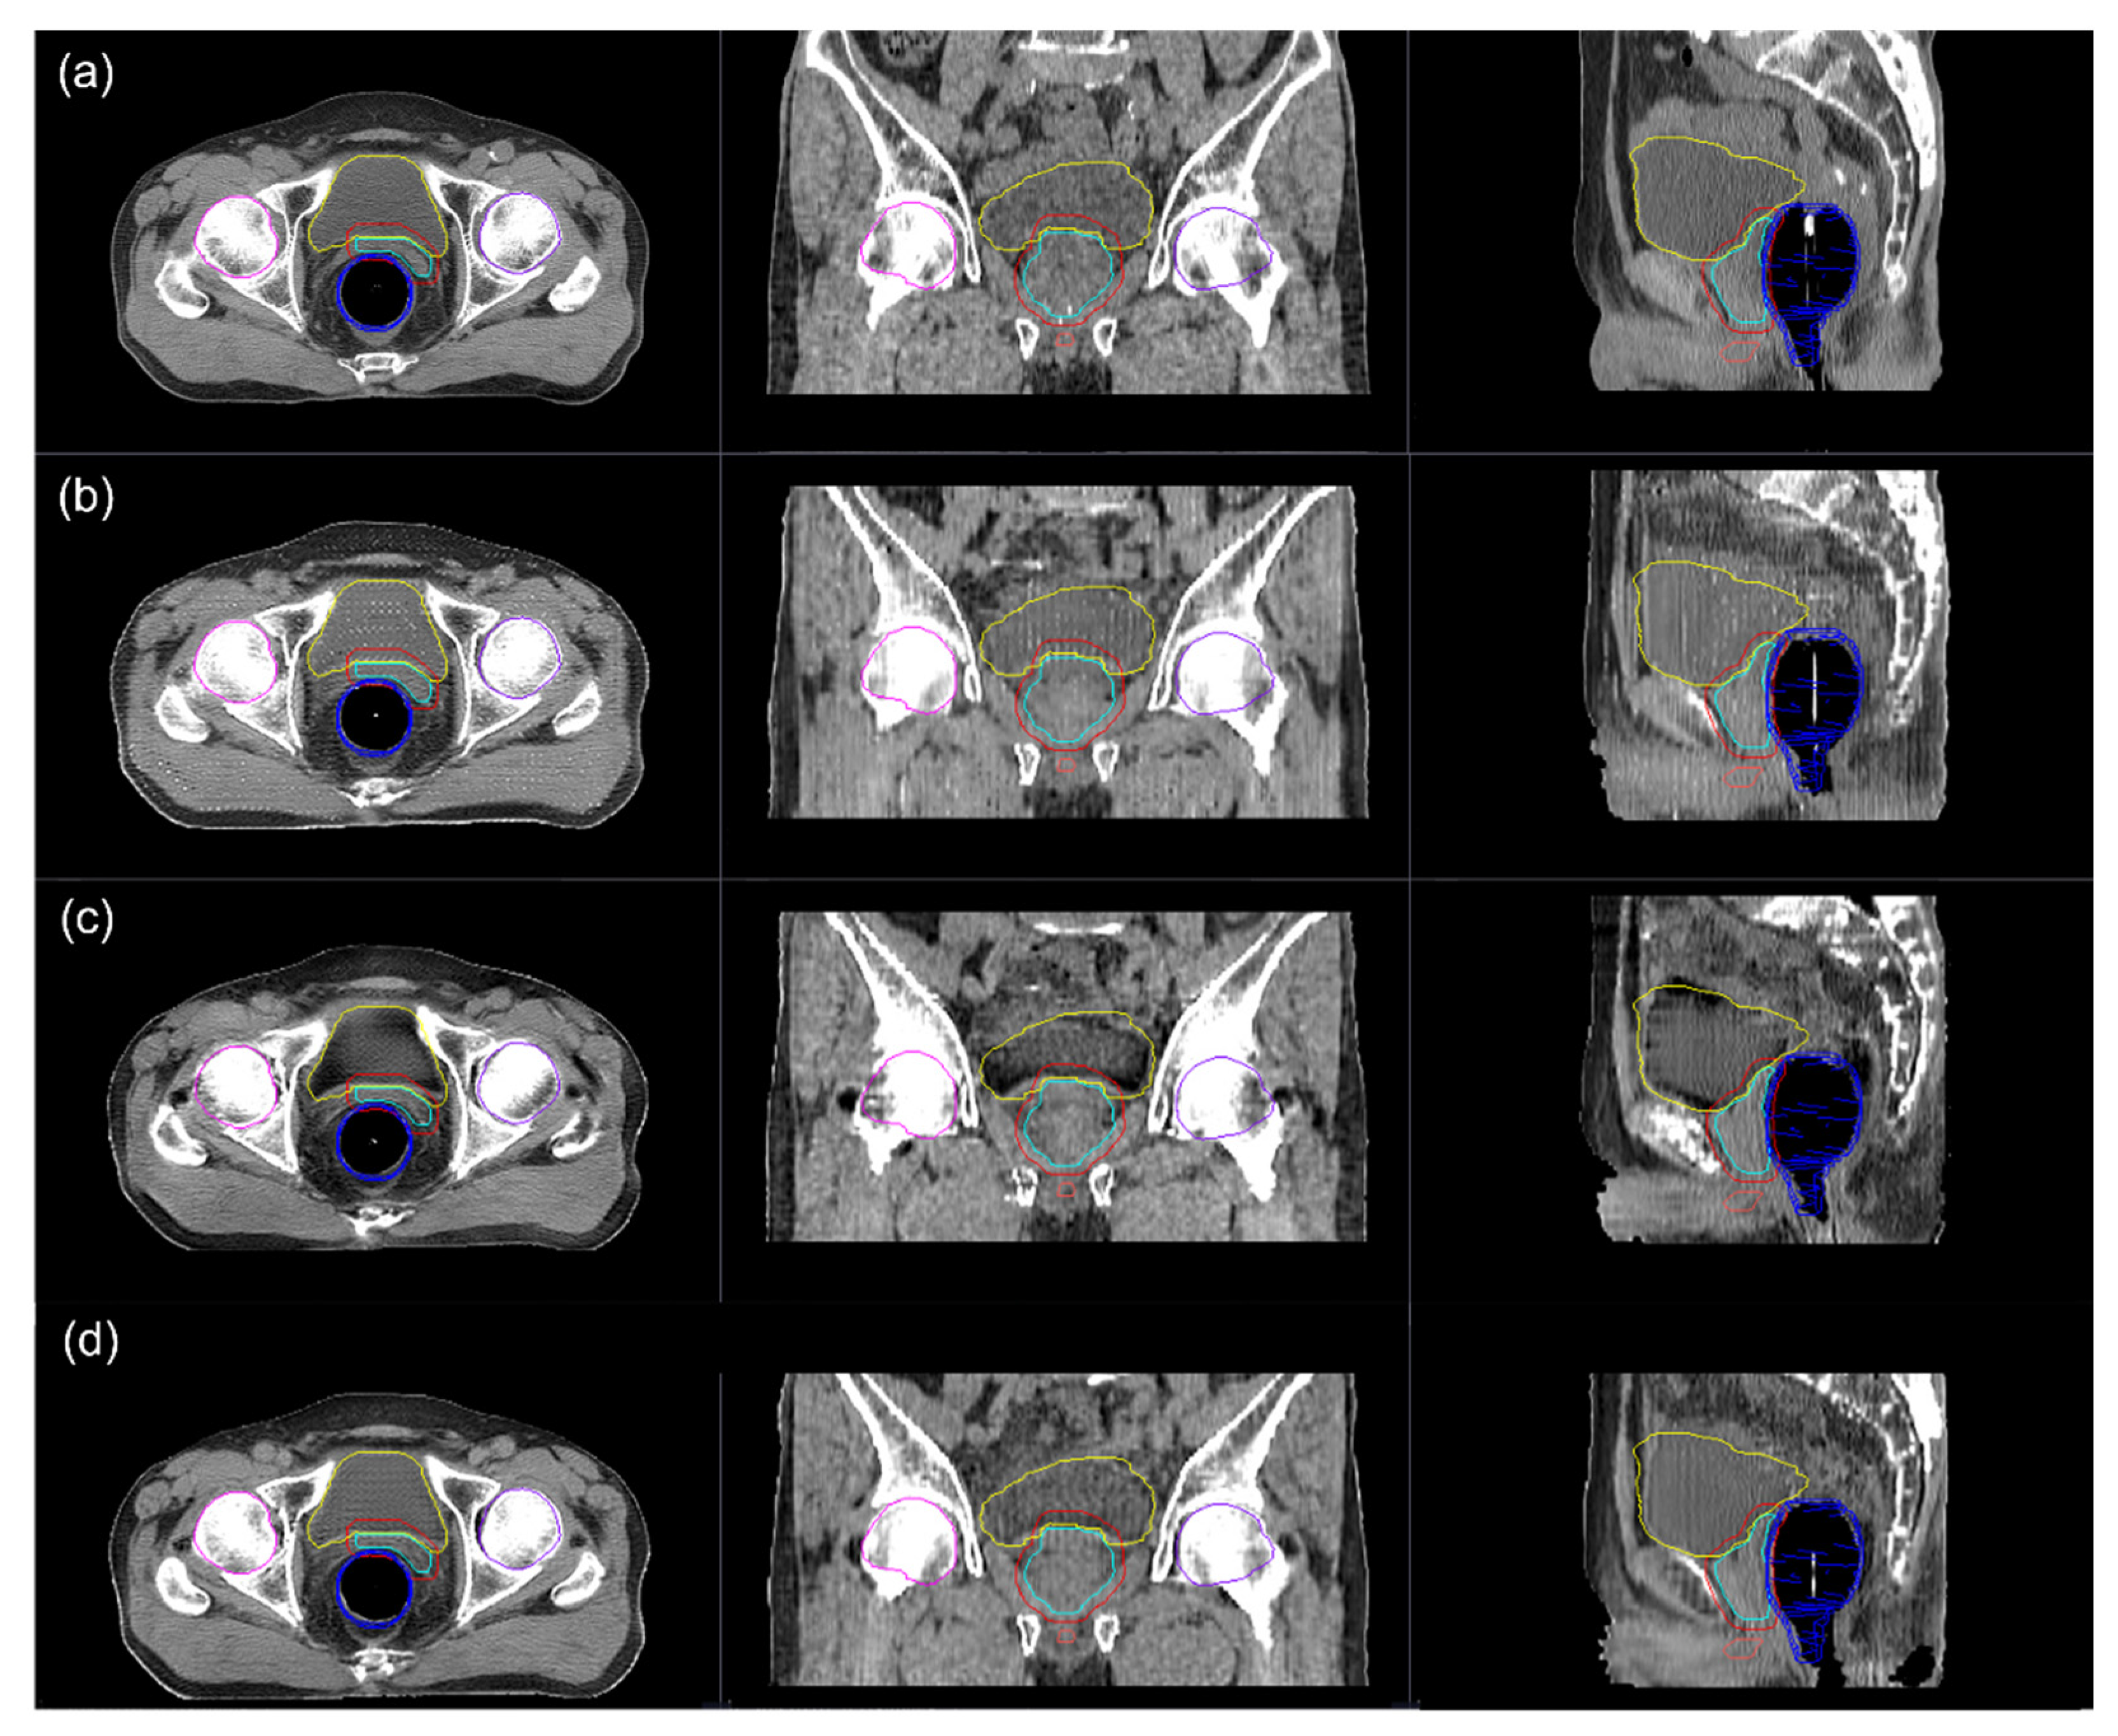

3.2. Image Quality

3.3. Dosimetric Comparison